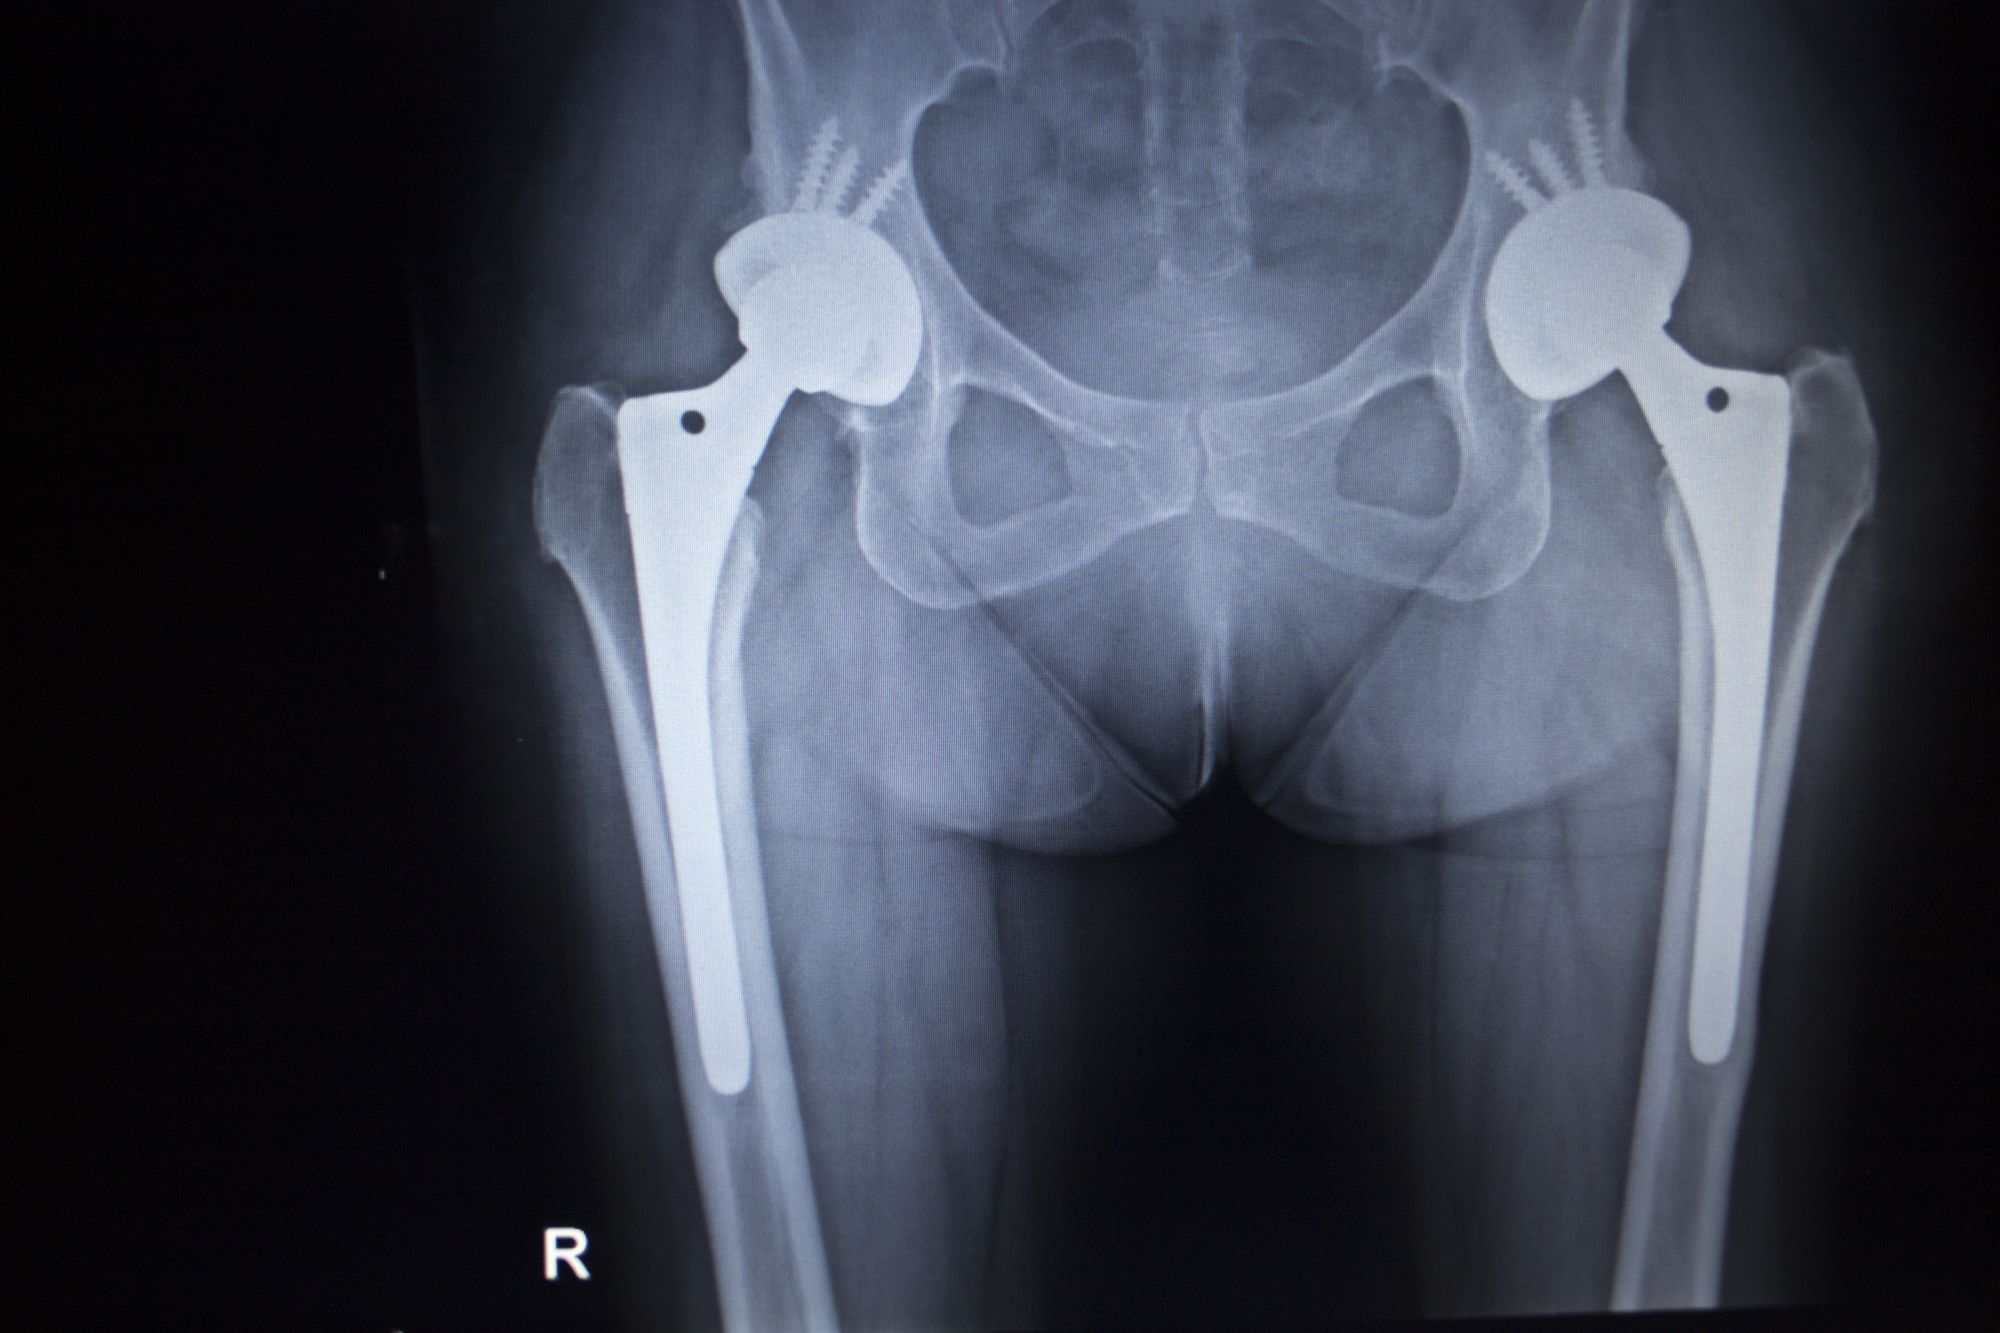

Stryker-recallProsthetic manufacturing giant Stryker Corporation has issued a voluntary recall of its LFIT metal hip implant after numerous complaints were submitted.

This Stryker recall affects seven different sizes of the LFIT V40 metal hip implants, with diameters ranging from 36 to 44 millimeters.

Like with previous metal hip implant recalls, the LFIT V40 hip implant had allegedly been shedding metal ions into the bloodstream at the ball and socket joint.

Also known as fretting, metal ions are shed into the bloodstream when the ball and socket joint components interact. This raises blood metal ion levels to dangerous heights, which causes tissue death and can negatively impact surrounding bone. This leads to further complications like pseudotumor formation, device failure, and infection.